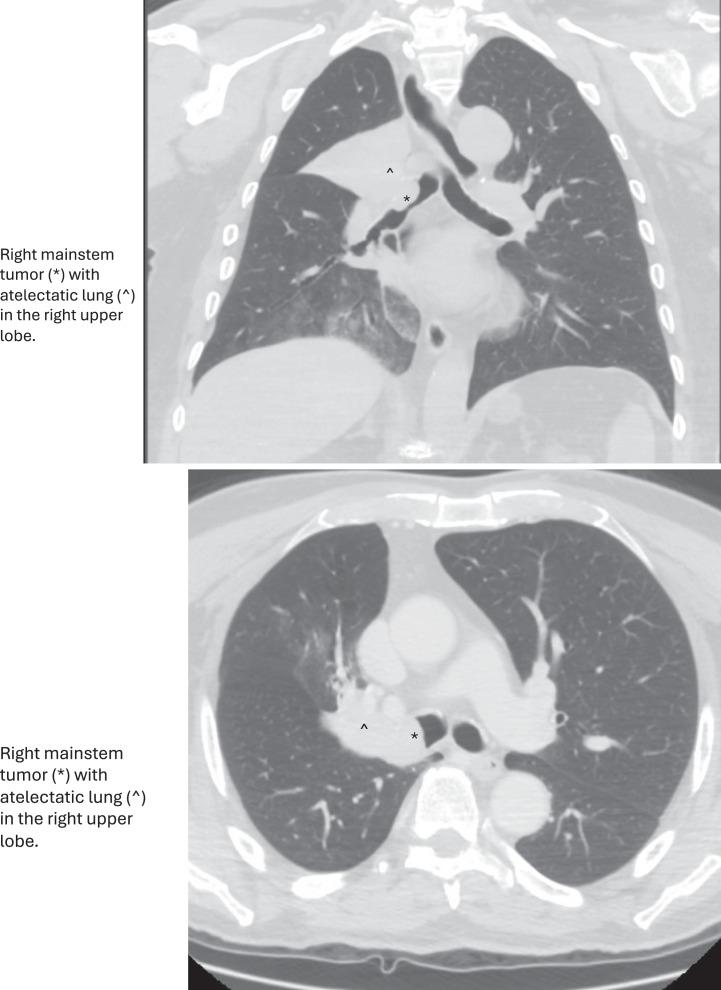

CASE PRESENTATION

In this case report, we present an 83-year-old male who presented with 2-day history of hemoptysis and subsequently diagnosed with a right upper lobe carcinoid tumor on pre-excision biopsy. After evaluation of the entire excised specimen, the tumor was subsequently reclassified as LCNEC. This case is rare as the tumor displayed pathologic features of AC (areas with low mitotic activity and punctate necrosis) alternating with areas of LCNEC (high mitotic activity with sheets of necrosis). Subsequent molecular studies were more characteristic of AC, with no mutations detected in Rb1 or p53. The patient underwent surgical resection (right upper lobectomy with bronchoplasty and mediastinal lymph node dissection) to remove the tumor.

在本病例报告中,我们介绍了一名83岁男性,他有2天咯血病史,术前活检后被诊断为右上叶类癌肿瘤。对整个切除标本进行评估后,该肿瘤随后被重新分类为LCNEC。该病例罕见,因为肿瘤表现出AC的病理特征(有低有丝分裂活性和点状坏死区域)与LCNEC区域(高有丝分裂活性伴大片坏死)交替出现。随后的分子研究更具AC特征,未在Rb1或p53中检测到突变。患者接受了手术切除(右上叶切除加支气管成形术和纵隔淋巴结清扫)以切除肿瘤。